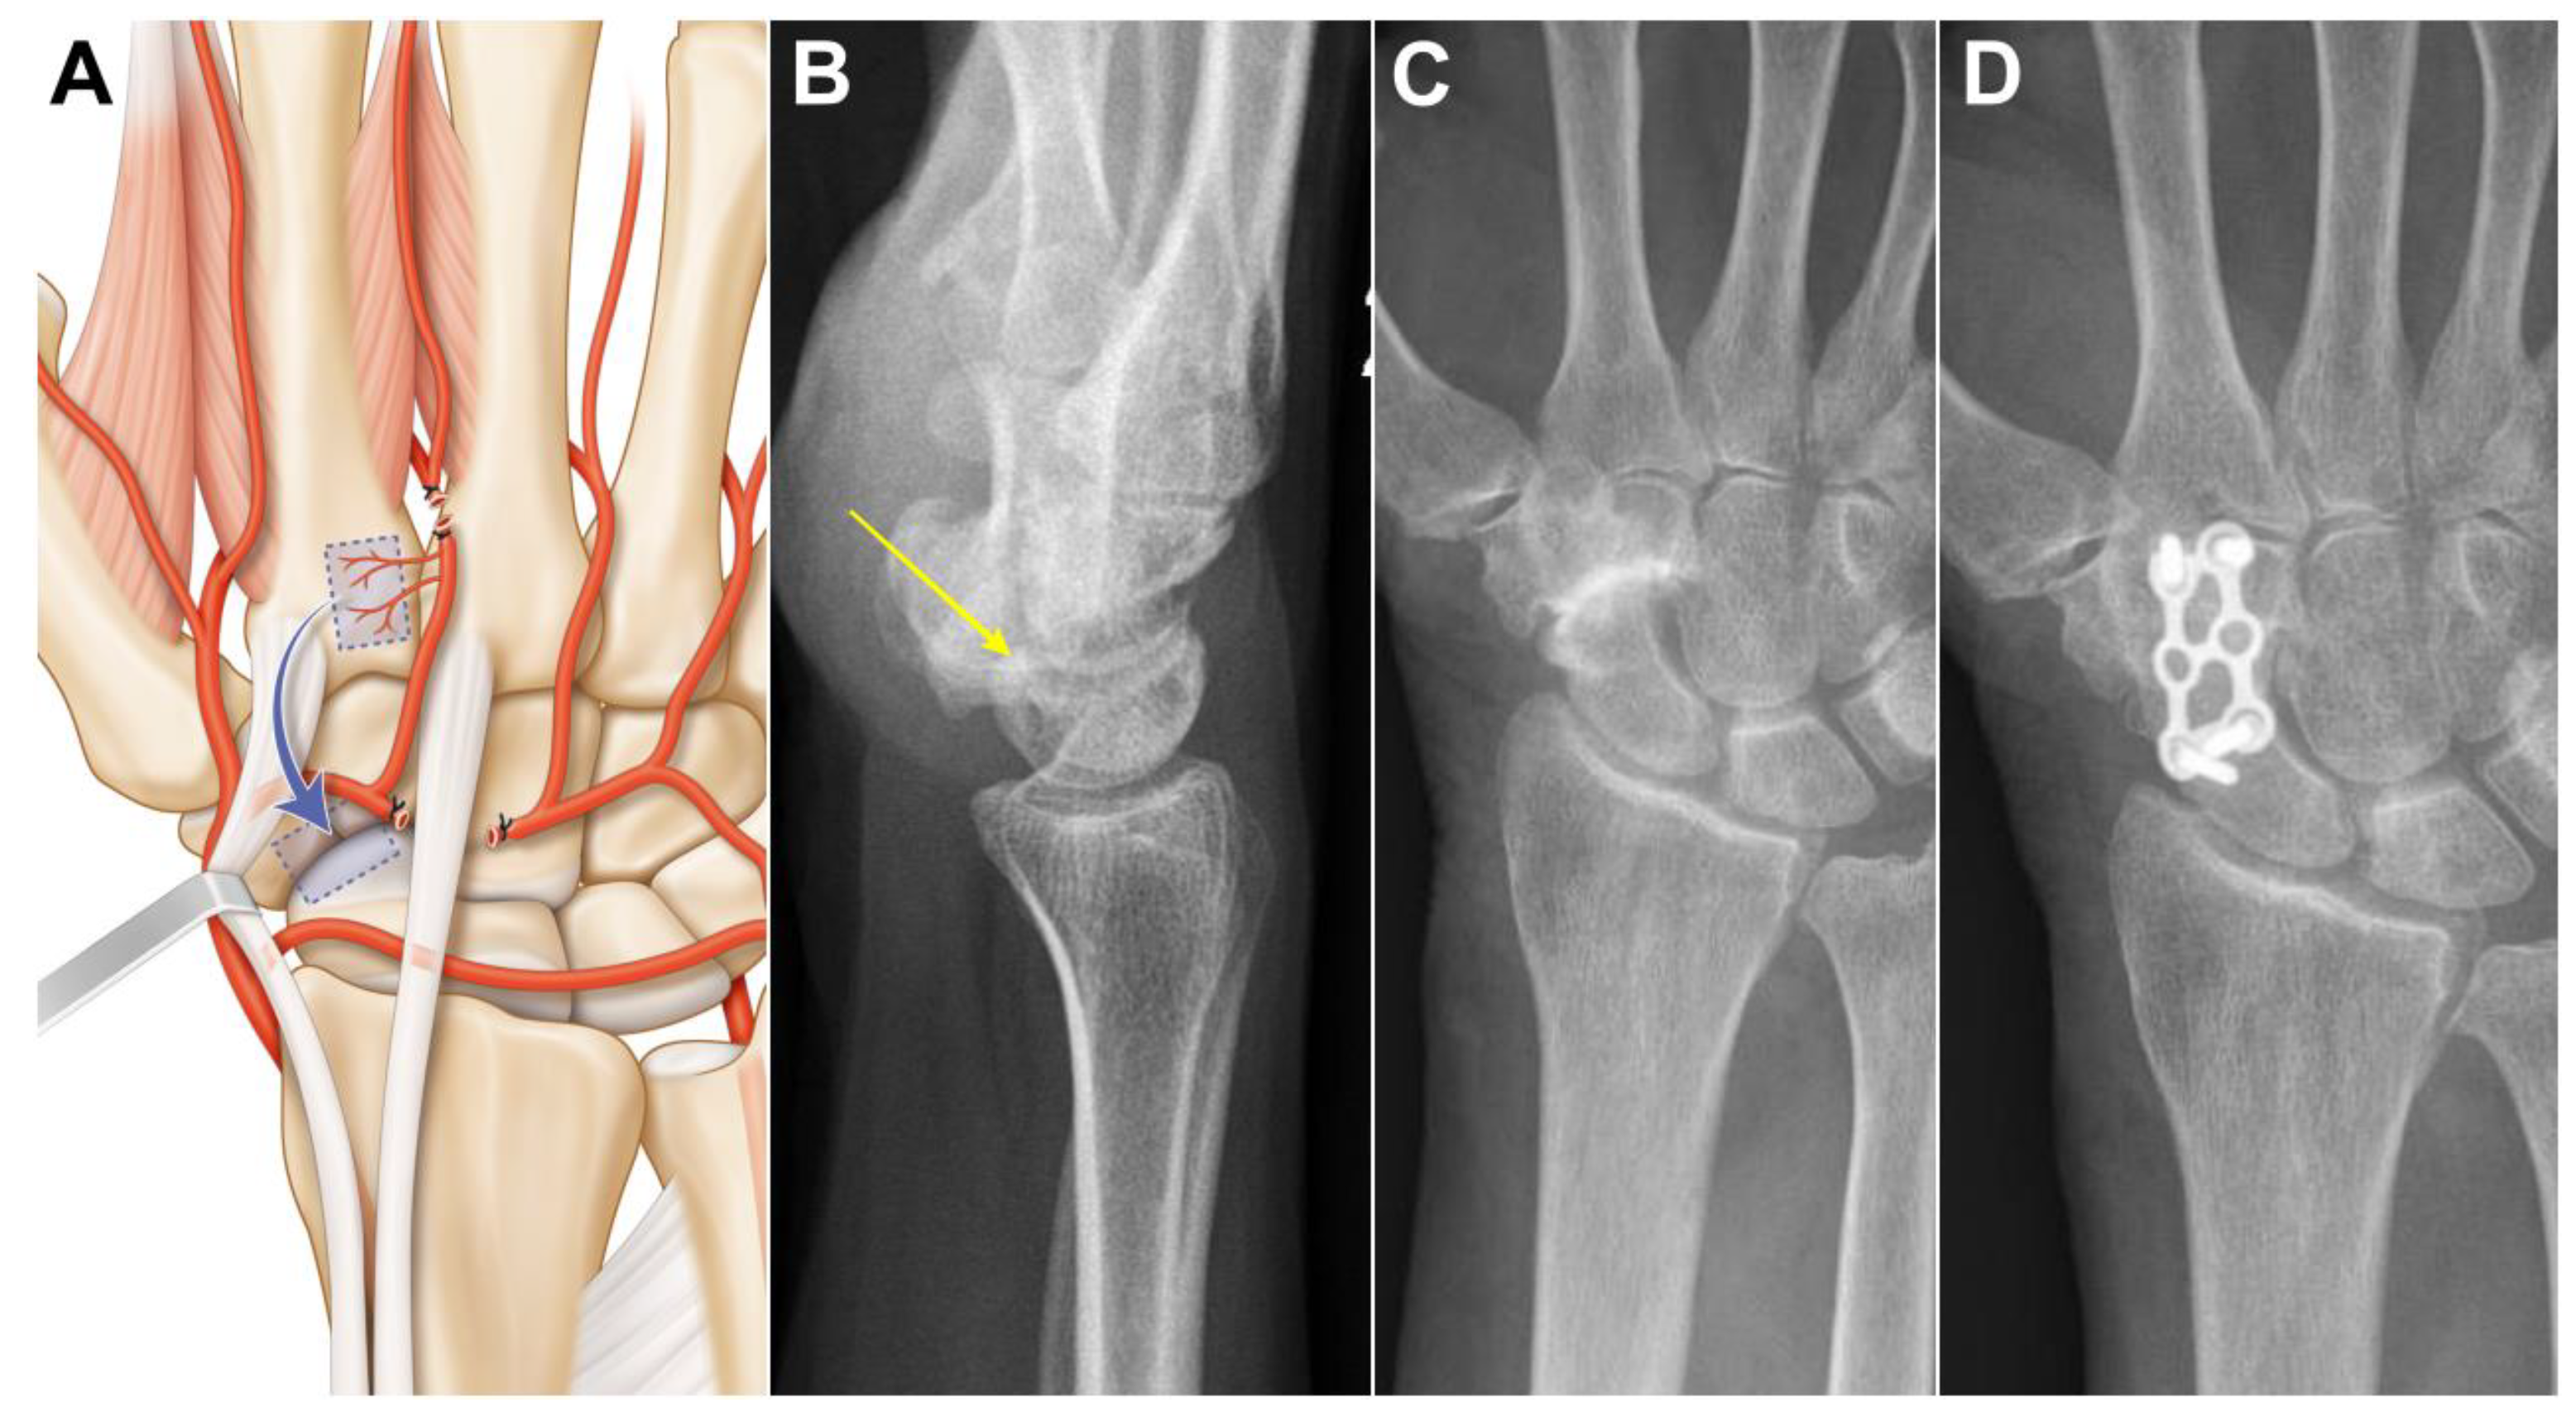

Case 1: A 73-year-old female suffering from long-standing left scaphotrapeziotrapezoidal arthritis. Surgery was proposed after failure of conservative treatment. The patient underwent a scaphotrapeziotrapezoidal bone fusion. A longitudinal incision was made in line with the 2nd metacarpal ray over the carpus. Anastomosis between the dorsal carpal arch and the 2DMA was verified, and the 2DMA was ligated distally to the base of the second metacarpal (Figure 3A). Bone, periosteum and 2DMA were harvested and proximally transferred. The size of the pedicled bone was 1.0 × 0.9 cm. The dorsal carpal arch was cut ulnarly to the 2DMA origin and released up to its origin at the radial artery for STT fusion. The 2DMA bone flap was pedicled on the radial side of the dorsal intercarpal arch and fixed with a plate and 2.0 mm screws (Aptus, Medartis, Switzerland). Union was obtained after 11 weeks (Figure 3B,C). No complications were observed at the donor and recipient sites. Clinical and radiological outcomes were unchanged 2 years after surgery.

Figure 3. Case 1. (A) Arterial anatomy, the radially based pedicle necessitates ligating distal and ulnar branches; (B,C) preoperative X-ray showing advanced scaphotrapeziotrapezoidal arthritis and no DISI (yellow arrow); (D) union is obtained in less than three months.